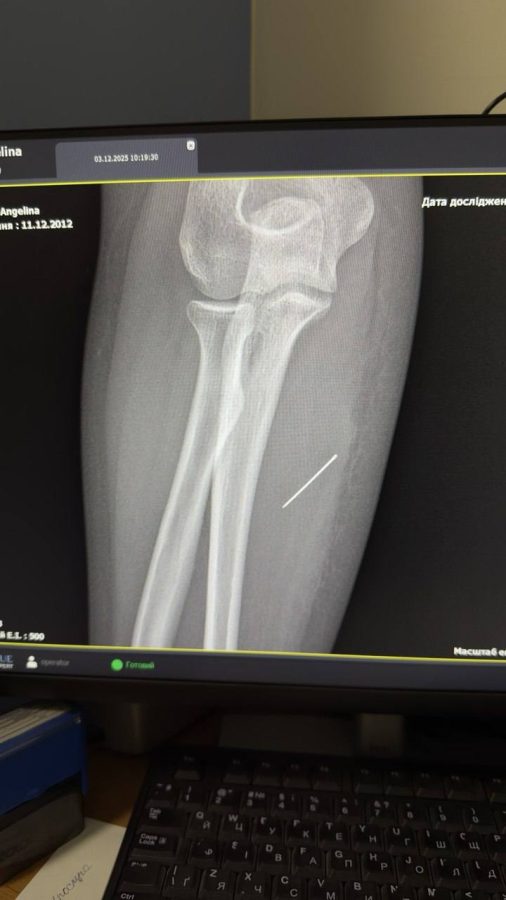

«Вже на рентгені лікарі чітко побачили, що голка зайшла під кутом 45 градусів і застрягла глибоко в товщі м’яза. Якби вона мігрувала ще далі, то могла б пошкодити або судини, або нервові закінчення», – наголошують у медзакладі.

Відтак за допомогою рентген-навігації ЕОП львівські хірурги точно визначили місце знаходження голки, невеликий розріз та правильно і безпечно її вилучили.